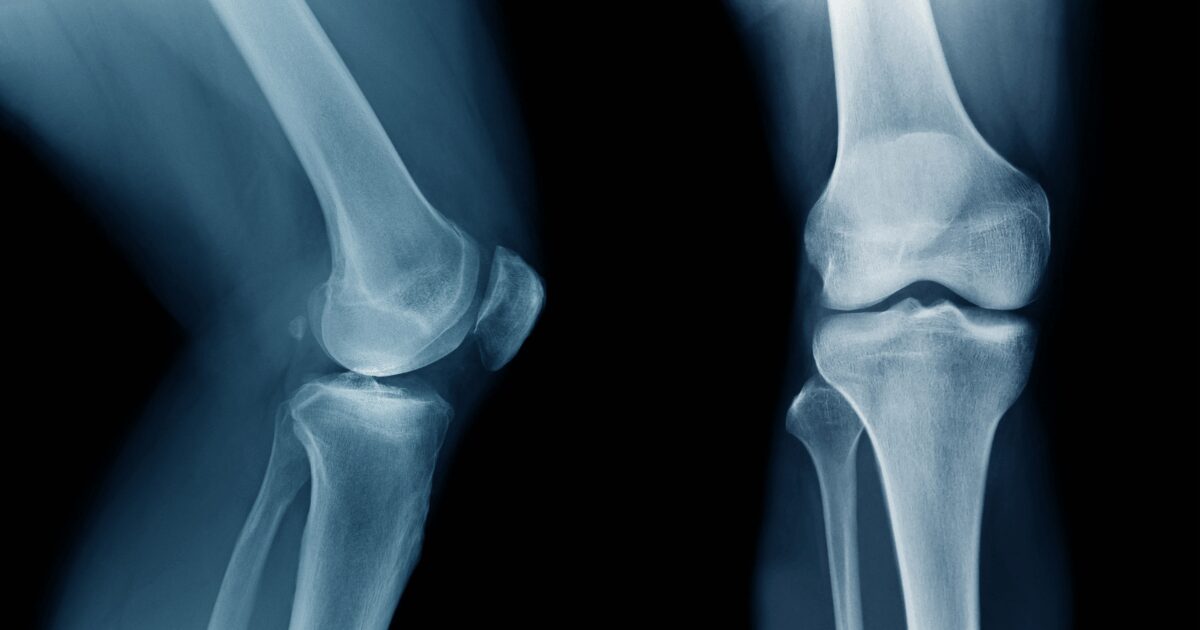

How Menopause Increases the Risk of Osteoporosis

“Estrogen protects your bones. Menopause triggers bone loss,” Dr. Watson explains. As estrogen levels decline, the balance between bone formation and bone resorption shifts, and not in your favor. This leads to a drop in bone mineral density (BMD), particularly in the first five years after menopause.

According to Dr. Watson, “Women lose about 50% of their trabecular bone and 30% of their cortical bone during the course of their lifetime.” That’s why postmenopausal osteoporosis is so common and why early action matters.

She warns that menopause-related bone loss is often missed because “osteoporosis is often called a ‘silent disease’, initially bone loss occurs without symptoms.”